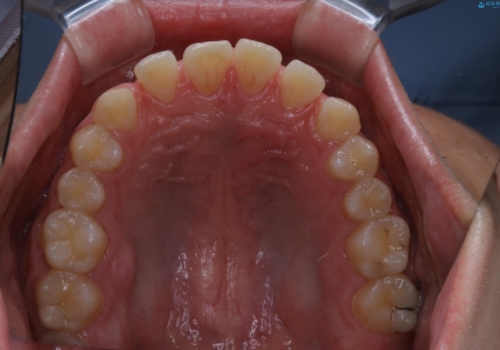

- 上のすきっ歯が気になるとご相談にいらした方です。上下顎ともにスペースがあったため、インビザラインFULLにて見た目と噛み合わせの改善も同時に行いました。

元々は上前歯のみの部分矯正をご希望されていましたが、下の歯もスペースがあり、噛み合わせ的にも上のみの部分治療は難しいことをお話ししました。前歯のみの部分矯正を行った場合、前歯の隙間だけが閉じて奥歯が噛めなくなってしまう場合もあります。インビザラインFULLにて治療することで、噛み合わせと見た目を同時に改善させることができ、大変喜んでいただけました。